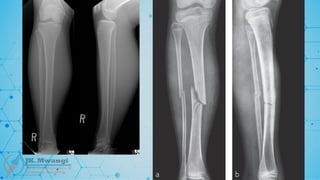

Maisonneuve fracture

 A spiral fracture of the proximal third of the fibula associated with an ankle injury,

typically a disruption of the syndesmosis. Named after Jules Germain François

Maisonneuve, who described it in 1840.

Jones fracture

 A fracture at the base of the fifth metatarsal, typically caused by inversion of the

foot. Named after Sir Robert Jones, who reported it in 1902 after fracturing his own

foot.